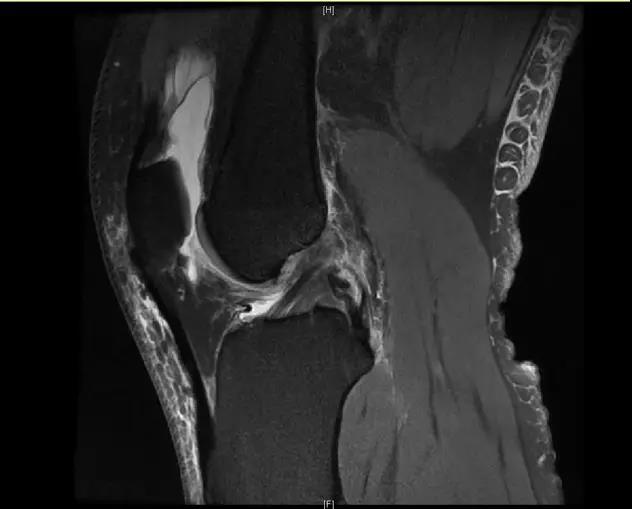

【有声病例】后交叉韧带断裂